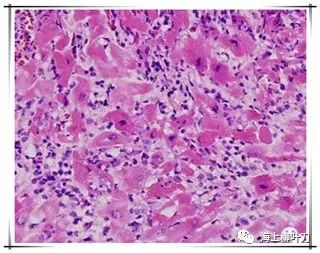

6.這是她的心肌病理切片,放大了100倍。

7.100倍還不是看得很清楚,放大400倍就很明顯了,一個(gè)個(gè)藍點(diǎn)就是淋巴球。這是很厲害的猛暴性心肌炎,整個(gè)心臟都被淋巴球浸潤了。